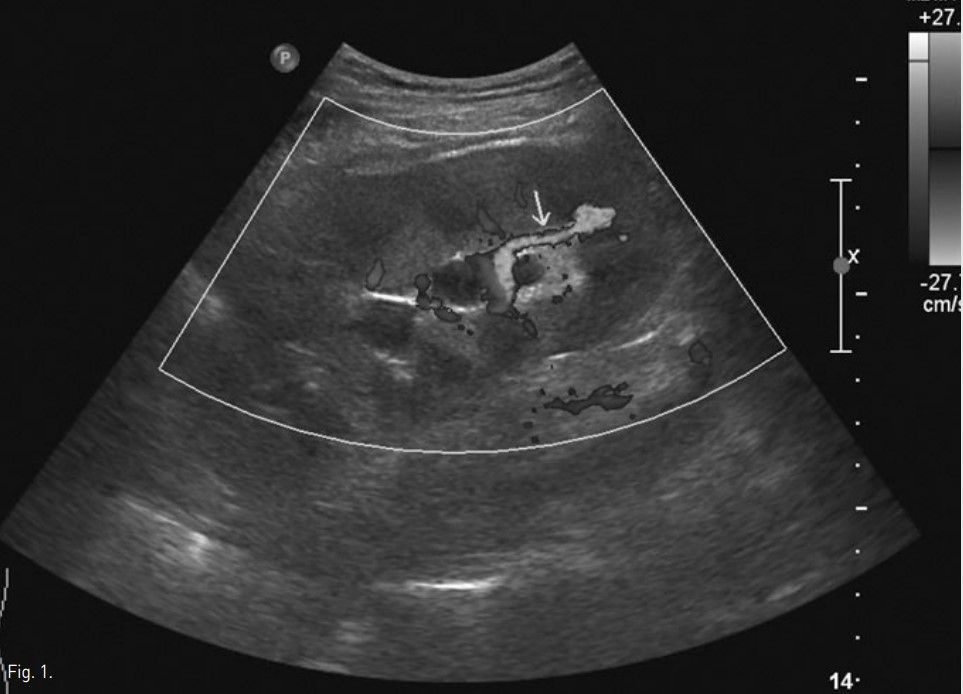

우하복부에 이식된 신장에 대한 초음파 검사상 신우, 신배와 요관의 확장과 함께 요관 원위부에 직경 15mm의 후방 그림자를 동반한 고에코 병변이 관찰되었고, 이는 원위부 요로 결석에 의한 수신증으로 진단되었다. 아울러 color doppler 초음파상 이식신의 하극(lower pole)에 혈액 와류(turbulent blood flow)가 관찰되고 분절동맥과 분절정맥의 연결과 함께 분절동맥 확장이 관찰되어 arteriovenous fistula도 진단되었다.

Fig. 1.

Color Doppler US shows arteriovenous fistula (arrow) in the lower pole of the transplanted kidney.